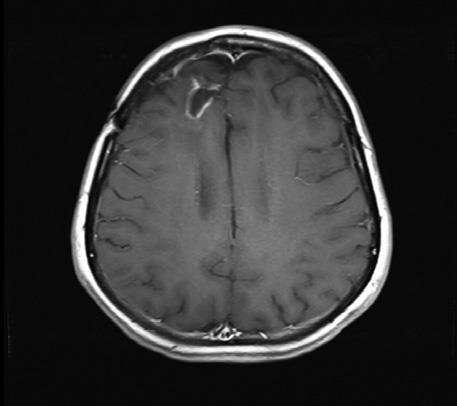

Энцефалограммы 20-летнего студента, которого лечат модифицированным вирусом полиомиелита (PVS-RIPO), вводимым через катетер, подсоединенный прямо к опухоли.

Слева – опухоль до лечения (затененная область в верхней левой части мозга). В середине – опухоль после двух месяцев лечения (она кажется даже больше из-за воспаления, вызванного иммунным ответом). Справа – опухоль, уменьшившаяся после девяти месяцев лечения.